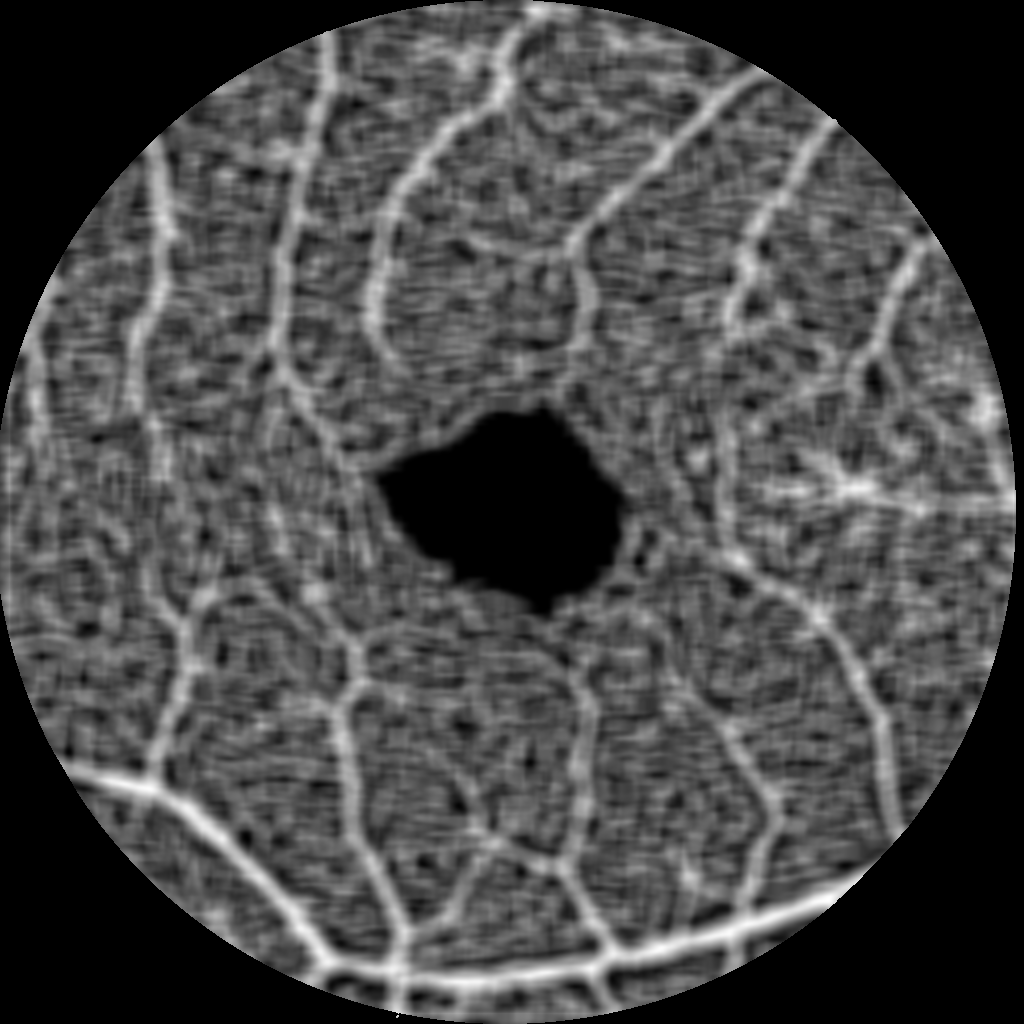

Our image segmentation is divided into three subtasks: the identification of small and big vessel and the FAZ. The final result, see Figure 2(b), is obtained by uniting the binary images with the small and big vessels and subsequently using the FAZ segmentation as a mask that excludes that area.

Refer to caption

(a) Original image

(b) Final segmentation

Figure 2: The combined substeps described in Sections 2.1 and 2.2 yield the final image.

The visual results of the segmentation are very good: small vessels are identified accurately, branches are preserved and the ratio of the vessel diameter is pictured realistically. Furthermore, small non-perfusion areas around larger vessel and vascular angles are also depicted truthfully. See Figure 4 for a visualisation of some details.